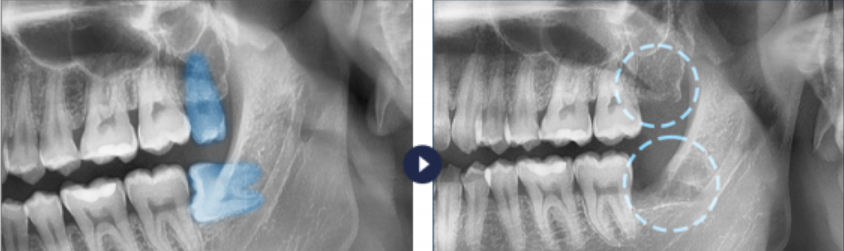

드라이 소켓은 우리가 사랑니를 포함한 치아를 뽑으면, 그 자리(발치와, Socket)에는 상처를 보호하고 뼈가 차오르는 데 필요한 '혈병(Blood Clot, 피떡)'이라는 소중한 젤리 같은 보호막이 형성됩니다.

이 혈병은 상처 위에 붙은 밴드와 같은 역할을 하여 잇몸뼈와 신경을 외부 자극으로부터 지켜주는 것이죠. 하지만! 이 중요한 혈병이 어떤 이유로 인해 떨어져 나가거나 녹아버려서 발치 부위의 뼈와 신경이 그대로 외부에 노출되는 상태를 바로 드라이 소켓이라고 부릅니다.

이름 그대로 소켓(발치 구멍)이 드라이(건조한)해진다는 뜻인데요, 마치 집의 지붕이 날아가서 내부 구조물이 바람과 비에 그대로 노출되는 상황과 같다고 할 수 있습니다.